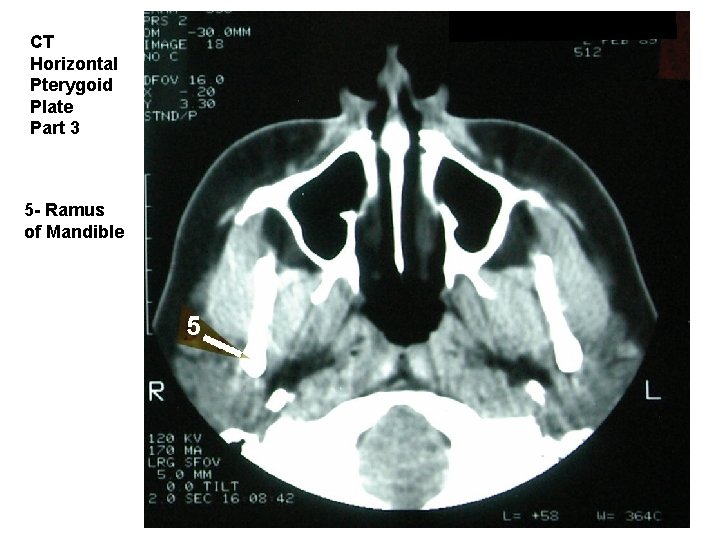

CT Horizontal Pterygoid Plate Part 3 5 - Ramus of Mandible

CT Horizontal Pterygoid Plate (three preceding slides) 1 - Nasal Septum 2 - Maxillary Sinus 3 - Medial Pterygoid Plate 4 - Lateral Pterygoid Plate 5 - Ramus of Mandible 6 - Lateral Pterygoid Muscle 7 - Neck of Mandible 8 - Coronoid Process of Mandible